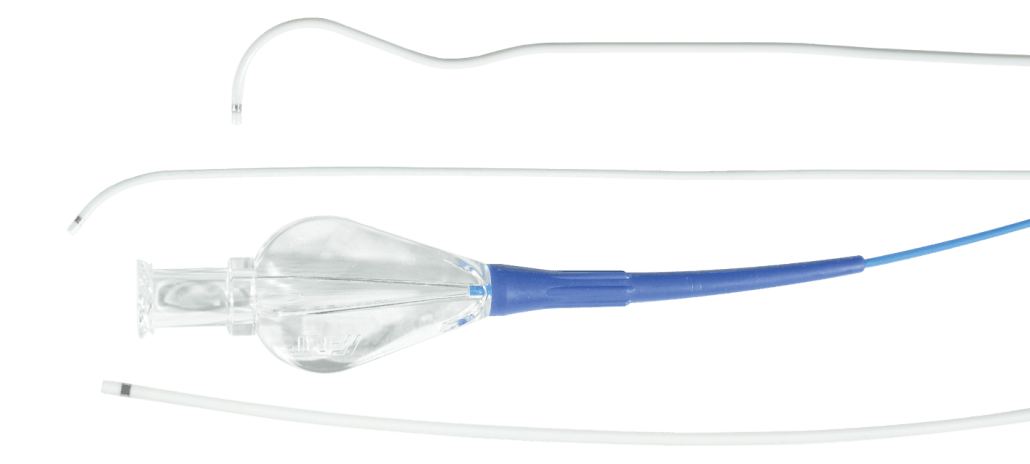

BENIGN PROSTATIC HYPERPLASIA (BPH)

Benign prostatic hyperplasia, or BPH, is the enlargement of the prostate gland and affects only men. It becomes more common as men get older. Up to 90% of men over the age of 80 have BPH. Although BPH is noncancerous, it can cause bothersome lower urinary tract symptoms.

Explore the products we offer to support prostatic artery embolization (PAE), a minimally invasive option to treat BPH.

MERIT PRODUCTS